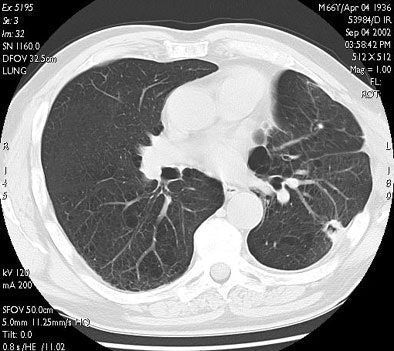

"Here you see the appearance of a treated lesion of the 12-month study period, as well as lesion enhancement values at the respective time points," Wallace said. "The ablated zone lesion initially appears larger, likely due to local inflammation. The lesion eventually becomes cavitary, and ultimately takes on the appearance of what looks like a scar on CT."

![]() |

| Transverse thin-section CT of a lingular segment nodule prior to RFA and one, three, and six months after RFA. (a) Baseline scan obtained prior to RFA shows a 2.2 x 2.8-cm nodule. (b) Scan one month after RFA shows marked interval increase in nodule size with early formation of a thick-walled cavity and adjacent anterolateral complicated hydropneumothorax. (c) Scan three months after RFA demonstrates interval regression of cavitary lesion and resolving adjacent hydropneumothorax. (d) Scan six months after RFA shows further interval regression of cavitary lesion and resolved hydropneumothorax. Images courtesy of Drs. Robert Suh, Jonathan Goldin, and Amanda Wallace, UCLA School of Medicine, Los Angeles. |